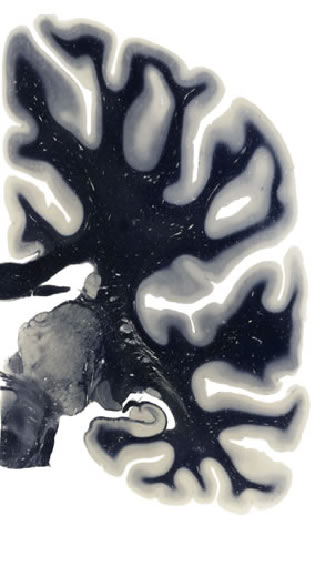

Hi-Resolution Sections · Cells (Nissl Staining) · Virtual Microscopy

Frontal sections (Nissl) from the Atlas Brain:

Macroscopy

Slice ID:

r3-0303

Plate NR:

44

Position:

29,2 mm